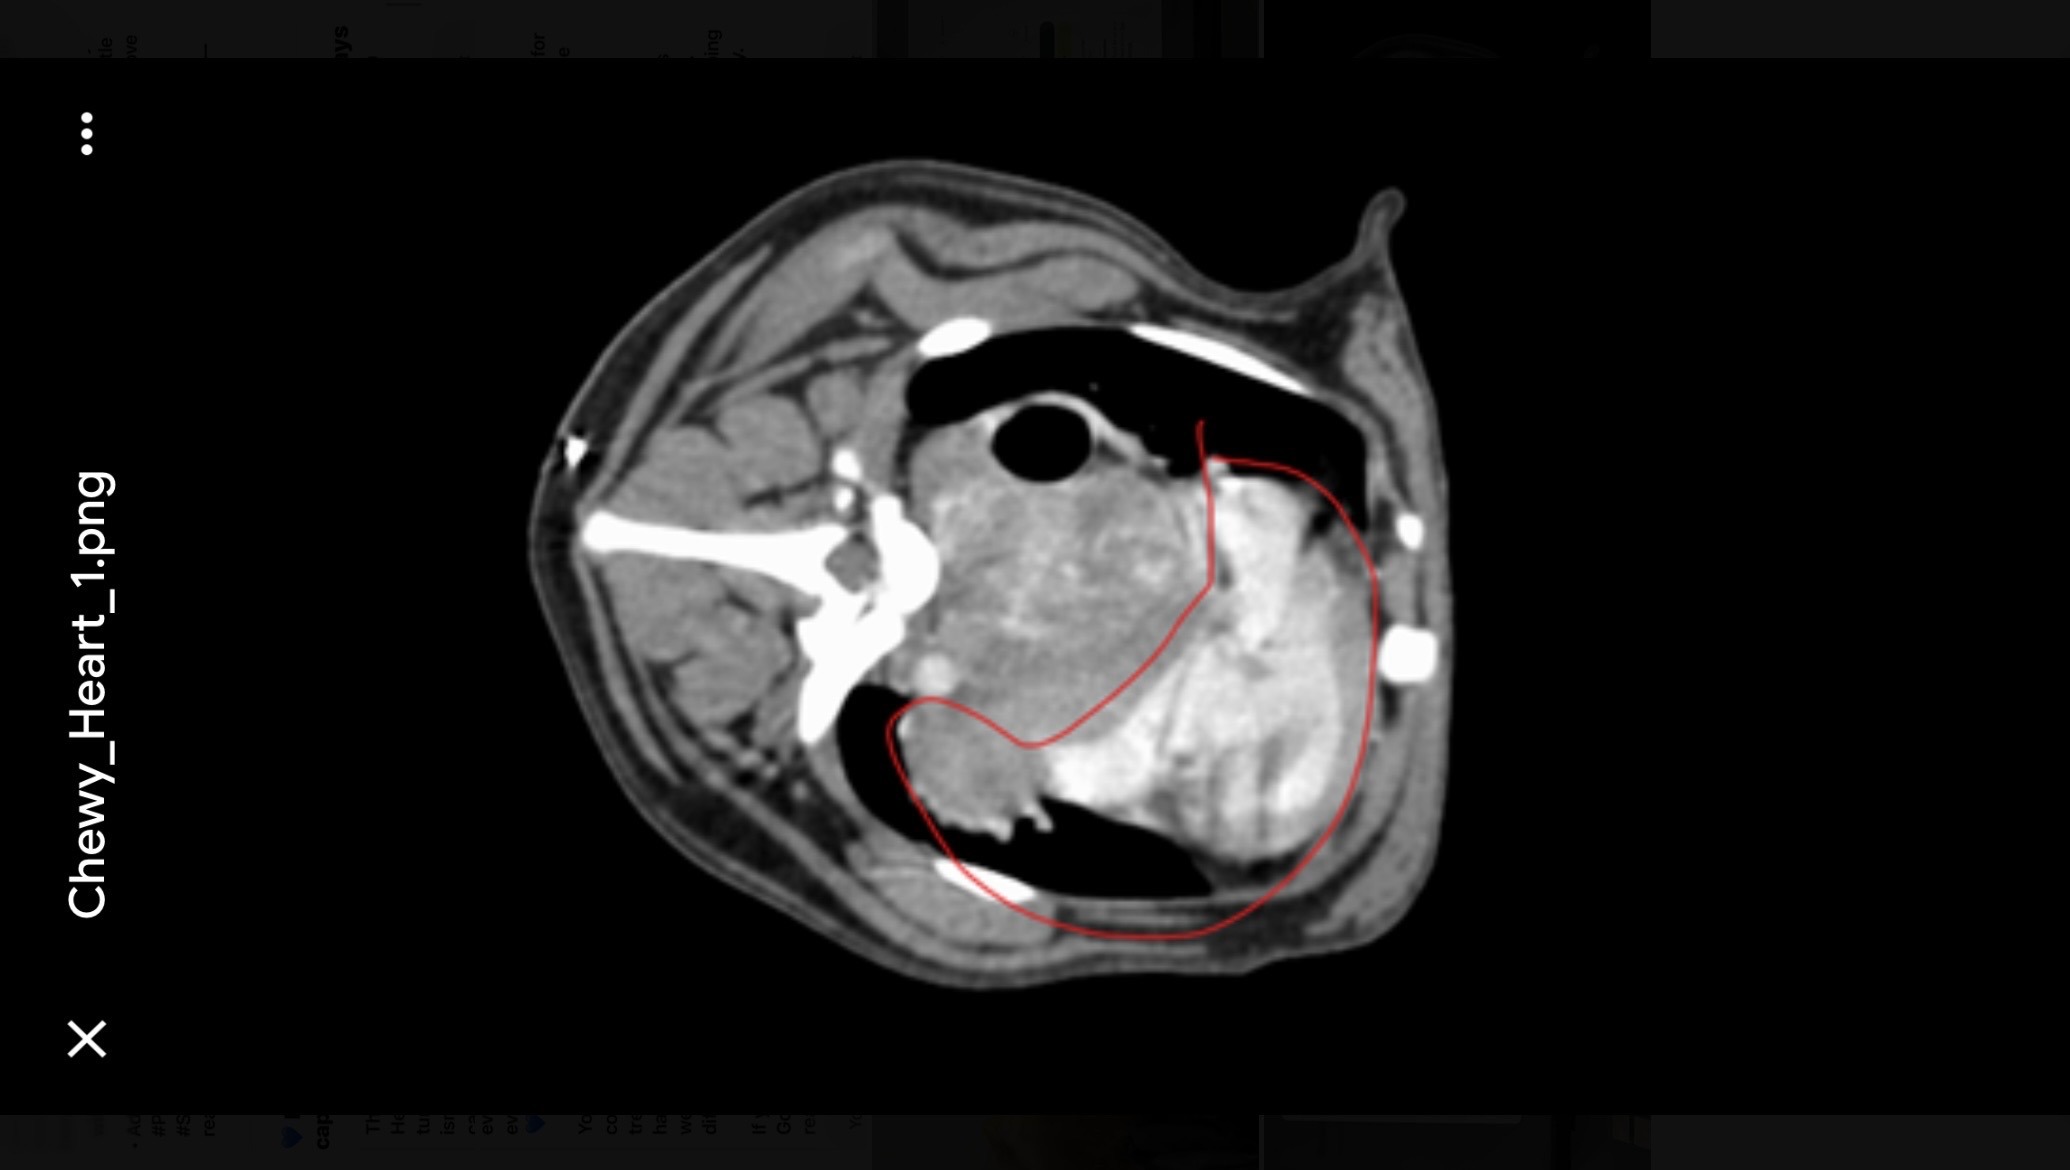

The specialist found a heart murmur and a large tumor pressing on his heart, called a chemodectoma. The mass is wrapped tightly around Chewy’s main blood vessels, including the aorta and pulmonary arteries. Because of its location, it’s too dangerous to biopsy, and surgery isn’t an option, it would be life-threatening.

The tumor is potentially malignant, but even if it’s benign, it’s still life-threatening because it compresses his heart and restricts blood flow.